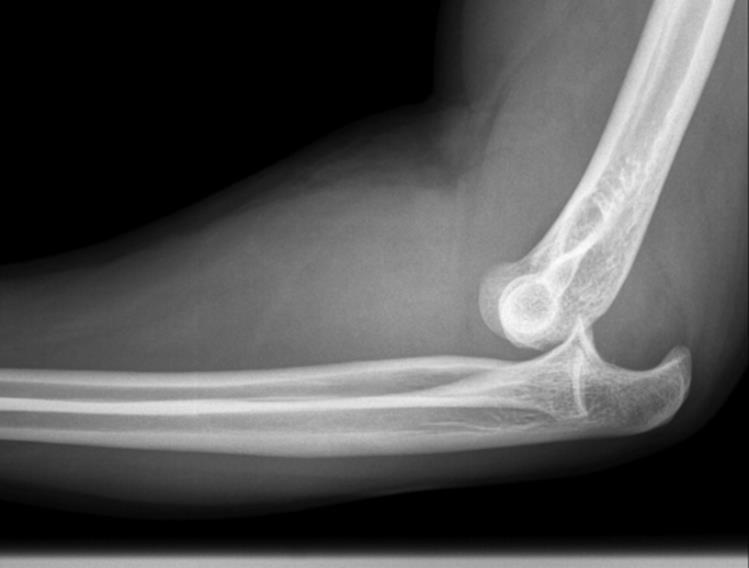

· Plain radiographs with a standard elbow series with AP and lateral projections are recommended (Figure 2.9)

Figure 2.9 Posterior elbow dislocation. (Reproduced with permission of the Department of Emergency Medicine, Feinberg School of Medicine, Northwestern University.)